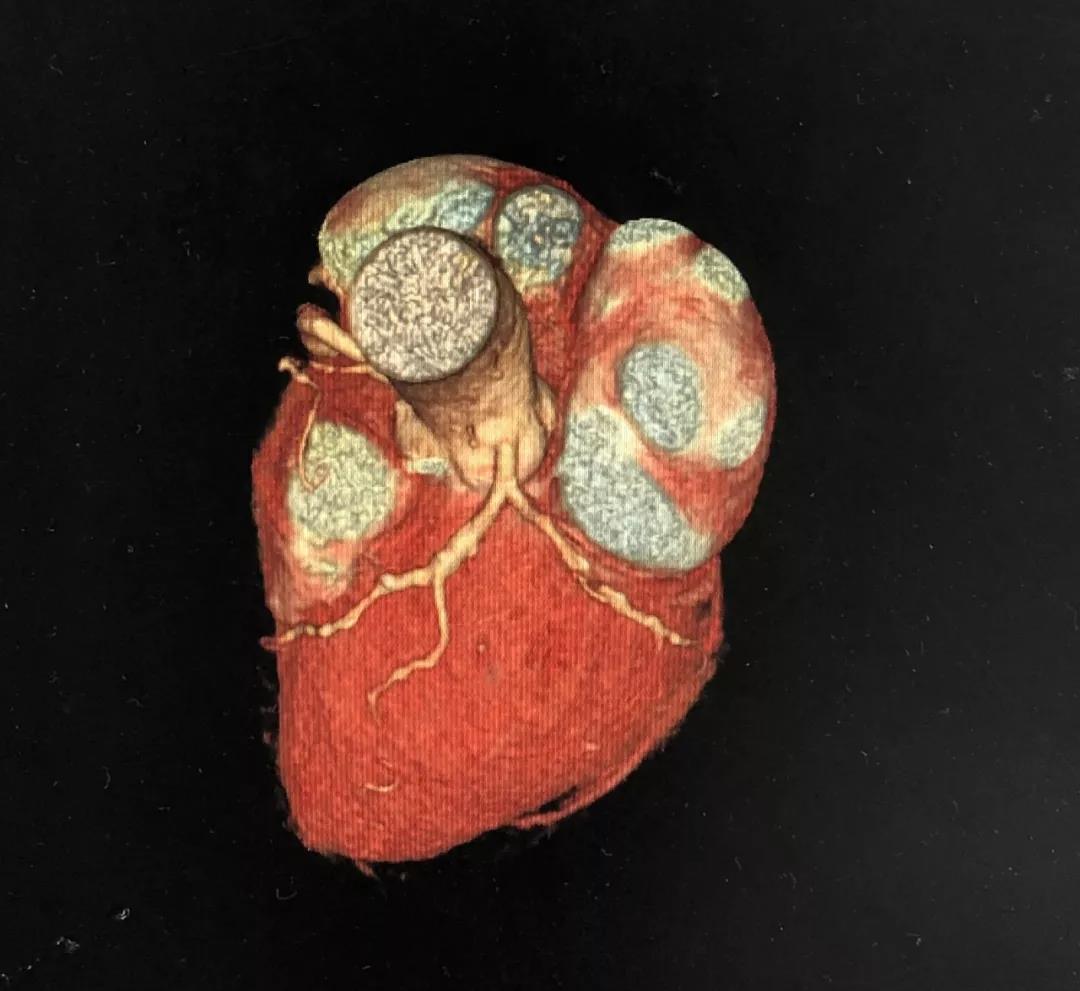

冠状动脉CTA

CCTA LAD病变特点:

近段血管较直

中远段血管偏细

中远段血管病变弥漫

病变段扭曲不很明显

病变段无重要分支发出

病变血管段有局灶点状钙化

CCTA LCX病变特点:

LM前分叉正常

LCX相对较直

中段病变伴局灶点状钙化